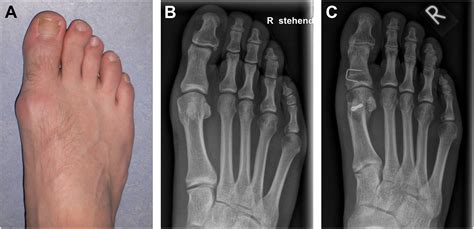

Diagnosing Mtp Joint Pain

Diagnosing Mtp joint pain typically involves a combination of physical examination and diagnostic tests. A healthcare provider will:

• Conduct a physical examination to assess the range of motion, tenderness, and any visible deformities.

• Order imaging tests, such as X-rays, MRI, or CT scans, to visualize the joint and surrounding structures.